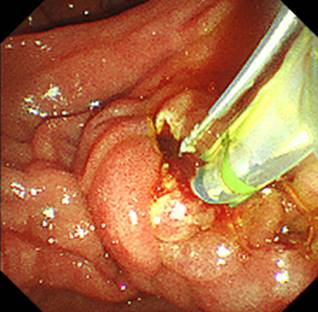

他院で治療困難とされた膵石。経口胆管膵管鏡下でEHLによる破砕の上で採石した。

また、当院では経口胆管膵管鏡を用いた結石治療も行っています。巨大な胆管結石や膵石に対して、経口胆管膵管鏡下で電気水圧衝撃波砕石術(EHL)を行い、結石を砕いて除去する治療を行っています。

術後の胆管空腸吻合部狭窄に伴う胆管結石だけでなく、通常の内視鏡治療では治療が難しい結石症例が他院から紹介され、当院で治療を行うことも多くあります。